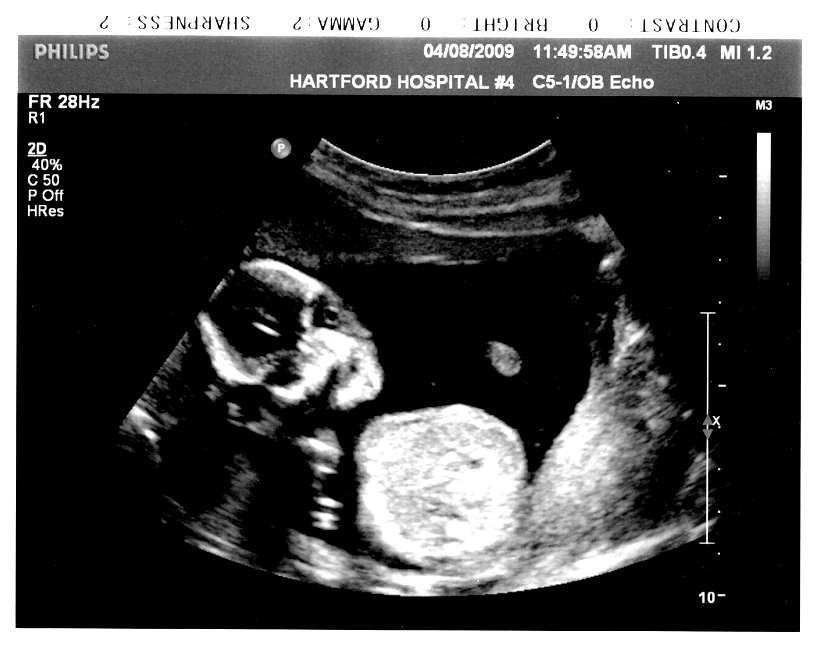

妊娠8か月(28、29、30、31週)の赤ちゃんの状態

身長約40cm、体重1400~1600g。

筋力がついてきて、胎動が活発な時期です。おなかの内側から思いっきり蹴りとばされて、ひいい、と悲鳴をあげたこともありましたが、不思議なもので、ますます愛情は深まるばかりでした(笑)。

皮下脂肪がついてきて、しわしわの皮膚に張りがでてきます。視力もよくなってきます。明暗の区別くらいはできるようになっています。

からだが大きくなったぶん、動ける範囲はせまくなって、子宮内での位置や姿勢はだいたい定まってきます。

脳も神経も内臓も発達しきっていますので、もしいま生まれてきたとしても、もう外界で十分に生きていくことができます。